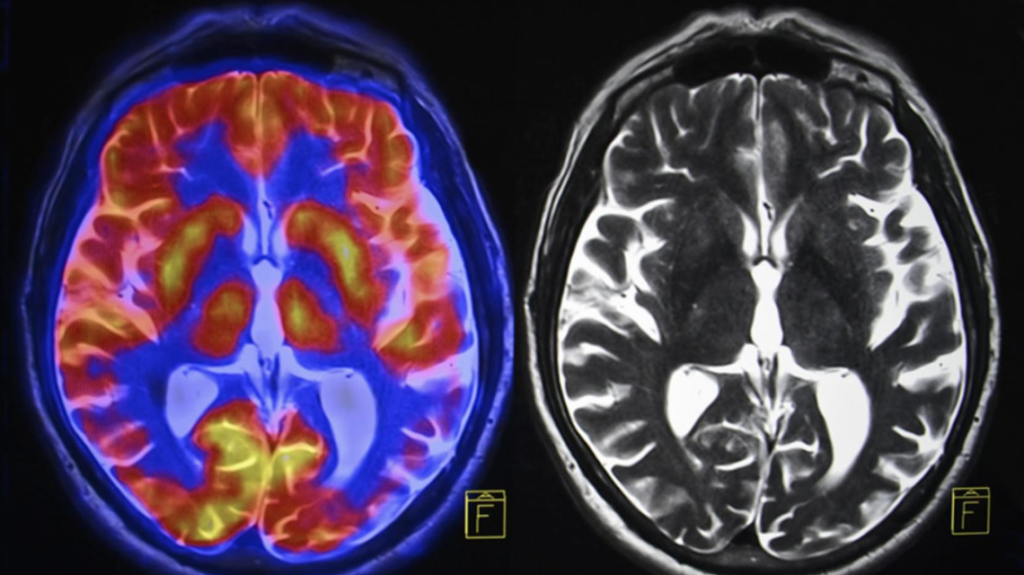

Brain wave therapy and coaching are exactly what executives, top-notch athletes and many celebrities are utilizing for peak performance. It is huge business now. These methods utilize electroencephalogram (EEG) brain monitoring equipment, neural feedback coaching, and brain training exercises. Yet … cha-ching! The majority of us do not have three thousand dollars for a one-month program!